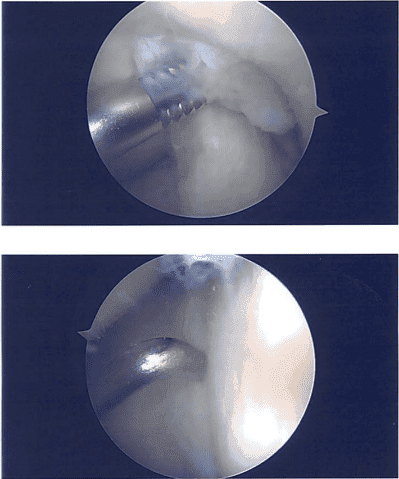

El examen del compartimento tibiofemoral lateral mostró una ruptura en el mango del cubo del menisco lateral, que se rotó hacia la muesca intercondilar. El menisco no podía reducirse fácilmente y se estiraba. El menisco se liberaba hacia adelante y hacia atrás en el nivel bueno. El menisco se redujo con dificultad.

Se insertó un espéculo para evitar lesiones en los aspectos posterior y medial de los haces neurovasculares. La reparación del menisco lateral se realizó utilizando suturas del revés usando cánulas específicas de zona x3, y se tomaron y se guardaron las fotos finales.

Imágenes intraoperatorias